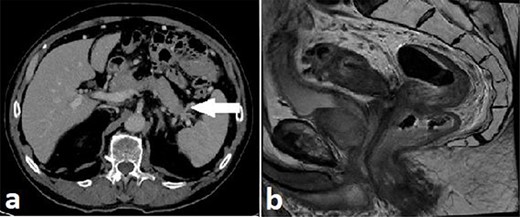

Routine staging for rectal cancer was performed. Magnetic resonance imaging (MRI) of the pelvis revealed an anterior rectal mass 7–8 cm from the anal verge with invasion into the seminal vesicles and at least three lymph nodes suspicious for metastases (cT4aN2). Computed tomography (CT) chest, abdomen and pelvis revealed enlarged nodes along the inferior mesenteric artery chain, but no definite metastatic disease was reported (Fig. 2). A 1.4 cm low attenuation hypo-enhancing mass in the distal pancreas occluding the splenic vein was reported as an incidental finding. Serum carcinoembryonic antigen (CEA) was 1.71ug/L and serum carbohydrate antigen 19-9 (Ca 19-9) was mildly elevated at 78u/ml.

Case A. Axial portal venous phase CT scan demonstrating hypo-enhancing distal pancreatic lesion encasing splenic vessels (a) and sagittal MRI pelvis demonstrating anterior low rectal tumour (b), staged as a cT4aN2Mx rectal adenocarcinoma.

Multidisciplinary team (MDT) discussion involving a pancreatic surgeon deemed a primary rectal adenocarcinoma with either incidental primary malignant or metastatic lesion in the distal pancreas as the likely diagnoses. Treatment recommended was neoadjuvant long-course chemoradiotherapy for the rectal tumour followed by rectal resection and distal pancreatectomy. Following neoadjuvant therapy restaging showed a slight reduction in size of pancreatic tumour from 14 to 12.6 mm and was again reported as consistent with a metastasis from a primary rectal malignancy. A laparoscopic ultra-low Hartmann’s procedure (gastrointestinal continuity not restored due to functional status preoperatively) combined with distal pancreatectomy and splenectomy was performed.